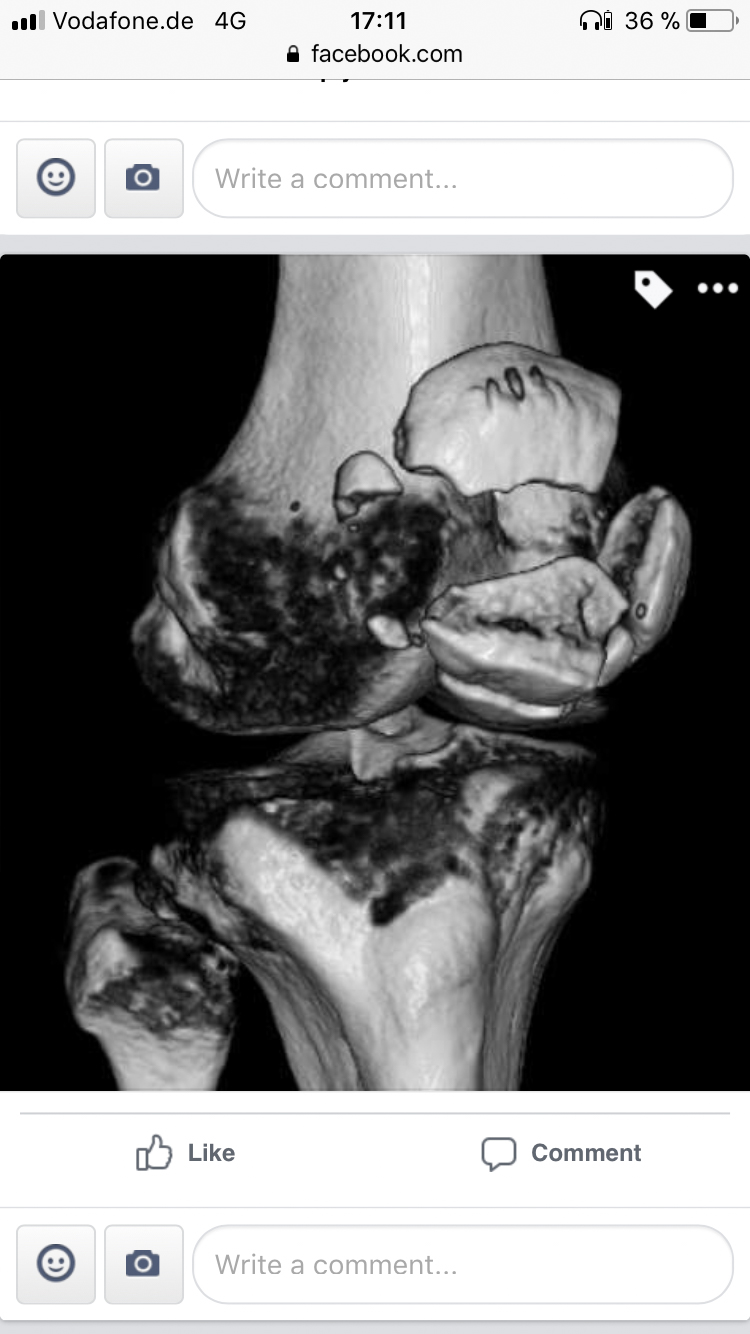

At BGU, I learned that my right kneecap – the patella – was literally in tatters. “It’s three parts and quite a lot of crumbs,” said one doctors. Another one compared it to “a bag of nuts”.

Both Mr Flum and I benefitted massively from a new operation technique devised by Munich-based medical company Arthrex: the so called “Patella Suture Plate”, which yields much better results than the traditional treatment involving tension band wiring.

The x-ray actually reveals a real piece of art – a total number of 10 (sic!) bolts plus the Arthrex’s “star plate” are holding the bits and bobs of my kneecap togehter.. These days, I’m largely pain free, have some 95 per cent of mobility back, and the knee is actually starting to look like one. It still feels a bit strange at times, but who cares about that? It does the job.